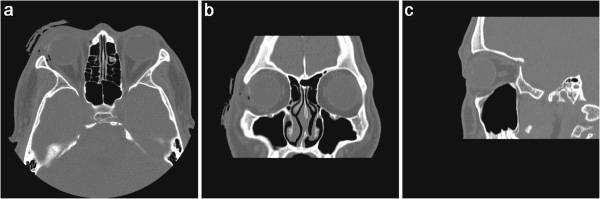

A 20-year-old man sustained a penetrating globe injury in the right eye while cleaning a blank cartridge pistol. His uncorrected visual acuity at presentation was hand motion and he had a flame burn of his right upper and lower lid with multiple missile wounds. On slit-lamp examination, there was a 12-mm laceration of conjunctiva along the 9 o'clock position with two pinhole-like penetrating injuries of cornea and sclera. There was also a 3-mm corneal laceration between 9 o'clock and 12 o'clock and the exposed lateral rectus muscle was split. Severe Descemet's membrane folding with stromal edema was observed, and numerous yellow, powder-like foreign bodies were impacted in the cornea. Layered anterior chamber bleeding with traumatic cataract was also noted. Transverse view of ultrasonography showed hyperechoic foreign bodies with mild reduplication echoes and shadowing. However, a computed tomographic scan using thin section did not reveal a radiopaque foreign body within the right globe.

To our best knowledge, this is the first case report of split extraocular muscle injury with traumatic cataract and penetrating ocular injury caused by blank cartridge injury. Intraocular foreign bodies undetectable by CT were identified by B-scan ultrasonography in our patient. This case highlights the importance of additional ultrasonography when evaluating severe ocular trauma. And ophthalmologists should consider the possibility of penetrating injury caused by blank ammunition.